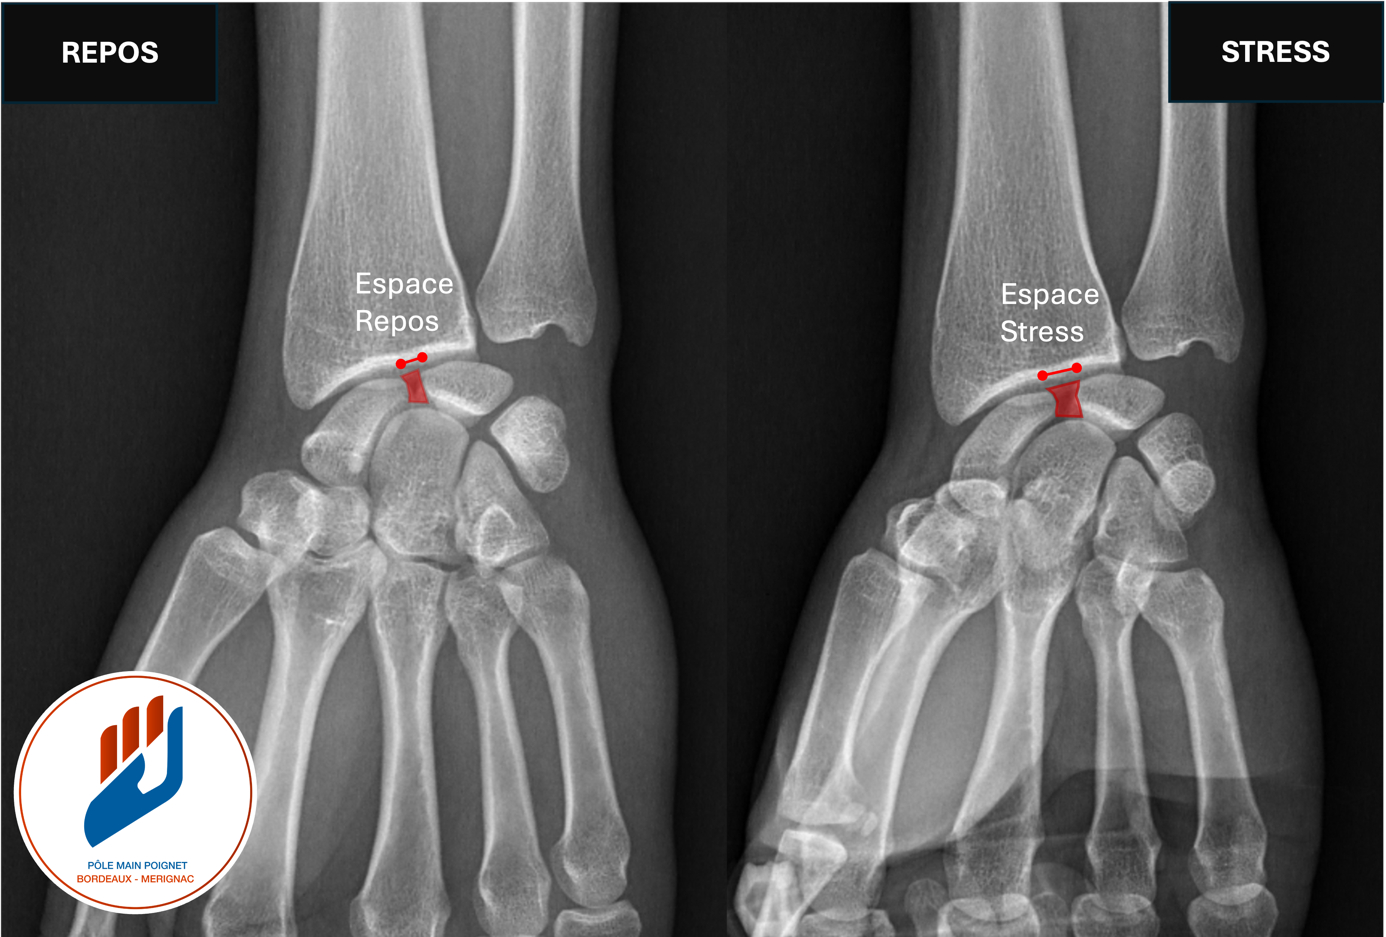

- Dynamique : instabilité apparaissant uniquement sur les examens dynamiques (échographie, radios en stress).

Radiographie dynamique du poignet: le cliché en stress dévoile une instabilité dynamique. L’espace entre le scaphoïde et le semi lunaire se majore en stress : Espace Repos < Espace Stress